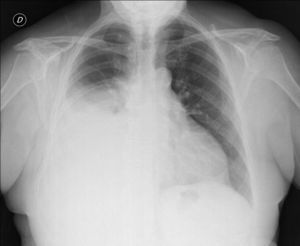

Diagnóstico de carcinoma broncogénico

El cáncer de pulmón constituye actualmente la primera causa de mortalidad oncológica a nivel mundial tanto en varones como en mujeres, fenómeno que obedece a una confluencia de factores biológicos,…